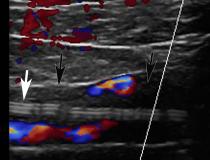

This photo gallery shows the variety of radiological presentations of COVID-19 (SARS-CoV-2) in medical imaging, including computed tomography (CT), radiograph X-rays, ultrasound, echocardiograms and magnetic resonance imaging (MRI). The radiology images show examples of typical COVID pneumonia in the lungs and the numerous complications the virus causes in the body in multiple organs, including the brain, kidneys, heart, abdomen and vascular system.

Ultrasound, especially hand-held ultrasound imaging devices, have become a primary imaging modality for novel coronavirus because of the ease to bag the device and sterilize it after use. CT and mobile X-ray systems are also used as front-line imaging systems for COVID-positive or suspected COVID patients.